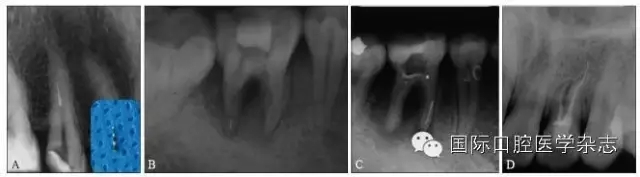

目前,對于分離器械周圍牙本質(zhì)厚度的評估以及取出后殘余牙本質(zhì)厚度的預(yù)測主要需借助影像學(xué)檢查,例如根尖片、錐形束CT(cone beamcomputed tomography,CBCT)圖像等。傳統(tǒng)的平行投照的根尖片無法反映三維立體結(jié)構(gòu),且往往存在解剖結(jié)構(gòu)影像的重疊,不利于臨床判斷,具有一定的局限性。多位學(xué)者[10]的研究表明:平行投照的根尖片會(huì)高估實(shí)際的牙本質(zhì)壁的厚度。一些學(xué)者[11-12]的研究表明:當(dāng)分離器械位于上頜第一磨牙近中根管時(shí),采用成角投照(21°)的拍攝技術(shù)與平行投照技術(shù)得到的X線片相比,能更準(zhǔn)確地評估牙本質(zhì)的厚度,為分離器械取出與否提供指導(dǎo)(圖4)。近年來,CBCT在牙髓病學(xué)中的應(yīng)用越來越廣泛,由于CBCT能清楚地反映牙及牙根周圍組織的三維立體結(jié)構(gòu),為牙本質(zhì)厚度的評估與預(yù)測提供了可行性(圖5);因此,CBCT在器械分離的病例術(shù)前風(fēng)險(xiǎn)評估方面具有較好的應(yīng)用前景。

A、B:采用平行投照技術(shù)獲得的圖像,模擬取出分離器械后殘余牙本質(zhì)的厚度,分離器械分別位于根管口下3 mm和5 mm;C、D:采用成角投照技術(shù)獲得的圖像,模擬取出分離器械后殘余牙本質(zhì)的厚度,分離器械分別位于根管口下3 mm和5 mm。

圖 4 平行投照與成角投照拍攝技術(shù)對牙本質(zhì)厚度的評估